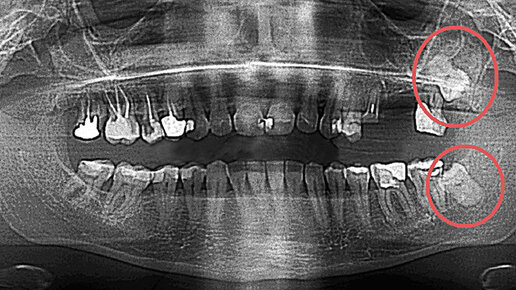

Зубы мудрости. Лечить или удалять?

"Это зуб мудрости и нет смысла его лечить". Именно эту фразу обычно мы слышим в кресле стоматолога. Но почему многие стоматологи так категорично относятся к данной группе зубов и "не хотят" лечить зубы мудрости? Ещё со времен муниципальной стоматологической поликлиники, когда не было разницы где лечить зубы, так как материалы практически не отличались, если пациент приходил к стоматологу-терапевту (далее терапевт) с жалобами на боли в зубе мудрости, то врач отправлял его к хирургу. Почему? Давайте разбираться...